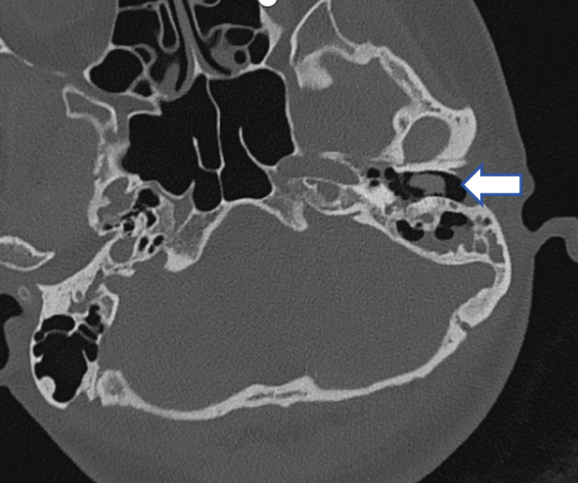

45岁的李女士,间断右侧搏动性耳鸣已经好几年,尤其在打哈欠时容易出现,轰轰声,与脉搏同步,耳朵里像装上了小马达。查看双侧外耳道、鼓膜都没有异常,进一步做了CT检查,发现:

CT示:右乙状窦憩室侵入右颞骨及乳突气房

初步诊断

血管性耳鸣、乙状窦憩室